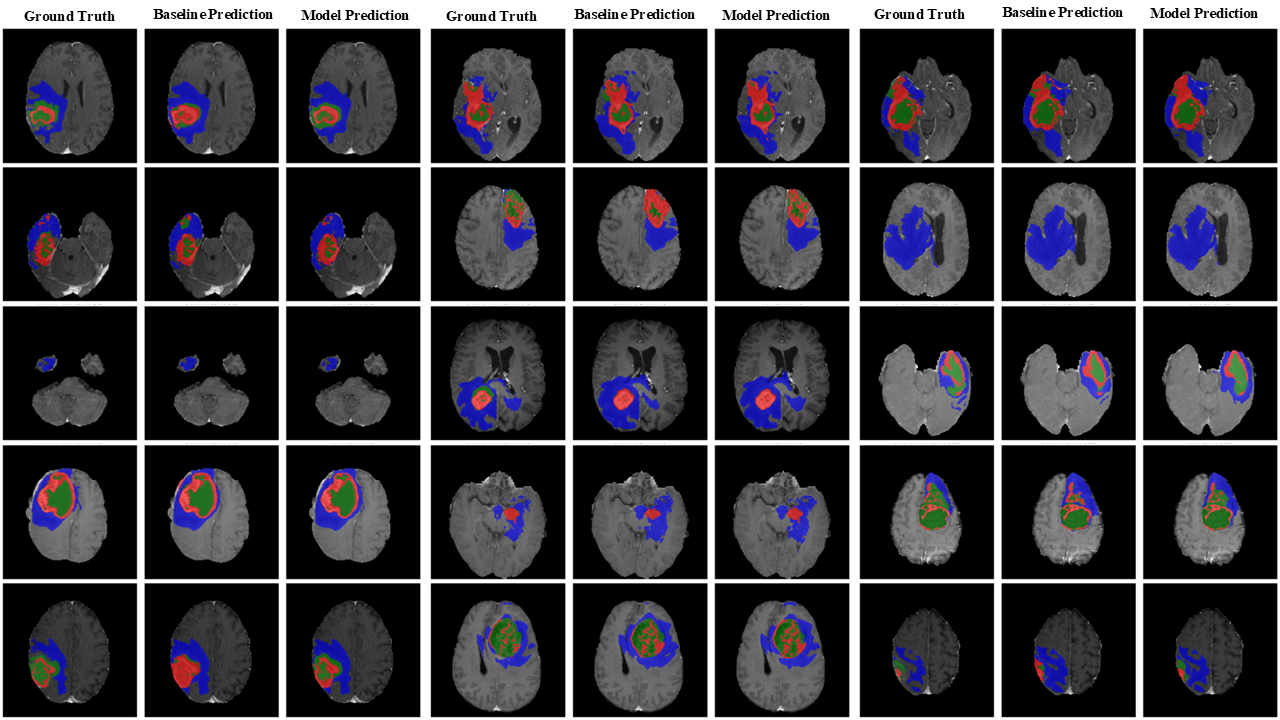

Refer to caption

Figure 8: Qualitative visualization of segmentation results produced by SwinUNETR on the BraTS18 dataset. Model Prediction is SwinUNETR + fuzzy, Baseline Prediction is SwinUNETR.

Figure 9: Qualitative visualization of segmentation results produced by SwinUNETR on the BraTS18 dataset. Model Prediction is SwinUNETR + fuzzy, Baseline Prediction is SwinUNETR.